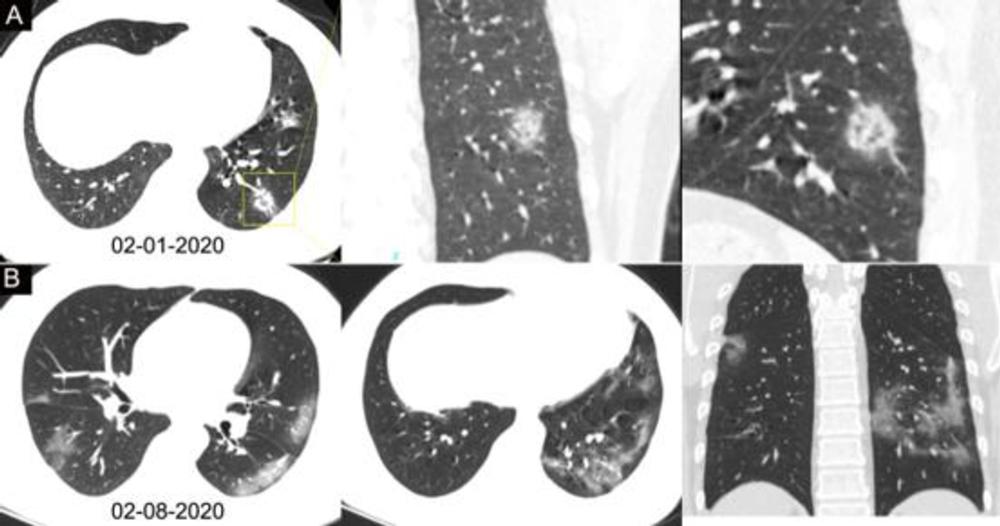

Figure 3. Chest CT images of a 34-year-old man with fever for 4 days. Positive result of RT-PCR assay for the SARS-CoV-2 using a swab sample was obtained on February 8, 2020. (A) Chest CT with lesion-magnified coronal and sagittal planes shows a nodule with reversed halo sign in the left lower lobe (yellow box) at the early stage of the pneumonia. (B) Chest CT with different axial planes and coronal reconstruction shows bilateral multifocal ground-glass opacities. The nodular opacity resolved.